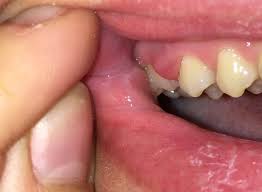

Dies ist so ein ovales Teil. Auch eine entzündete Kieferhöhle ohne einen erkrankten Zahn kann eine Schwellung oder Beule am Oberkiefer auslösen. Zahnfleischschmerzen können in allen Bereichen des Mundraums auftreten.

Das hintere Zahnfleisch also das Zahnfleisch hinter den Schneidezähnen ist auch irgendwie geschwollen ist auch etwas rot aber wie es aussieht nur äußerlich die Zähne selbst verursachen keine Schmerzen eben nur dieser Druck und das Gefühl dass sie zu groß sind. Der Wange ist abhängig davon inwieweit sich die Zahnwurzel entzündet hat. Meist bildet sich in dieser Zeit eine Beule am Zahnfleisch in direkter Nähe zum betroffenen Zahn.